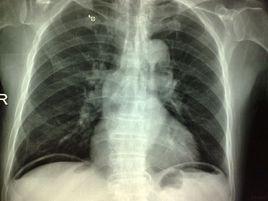

3.X線,B超,CT檢查,確診疾病。